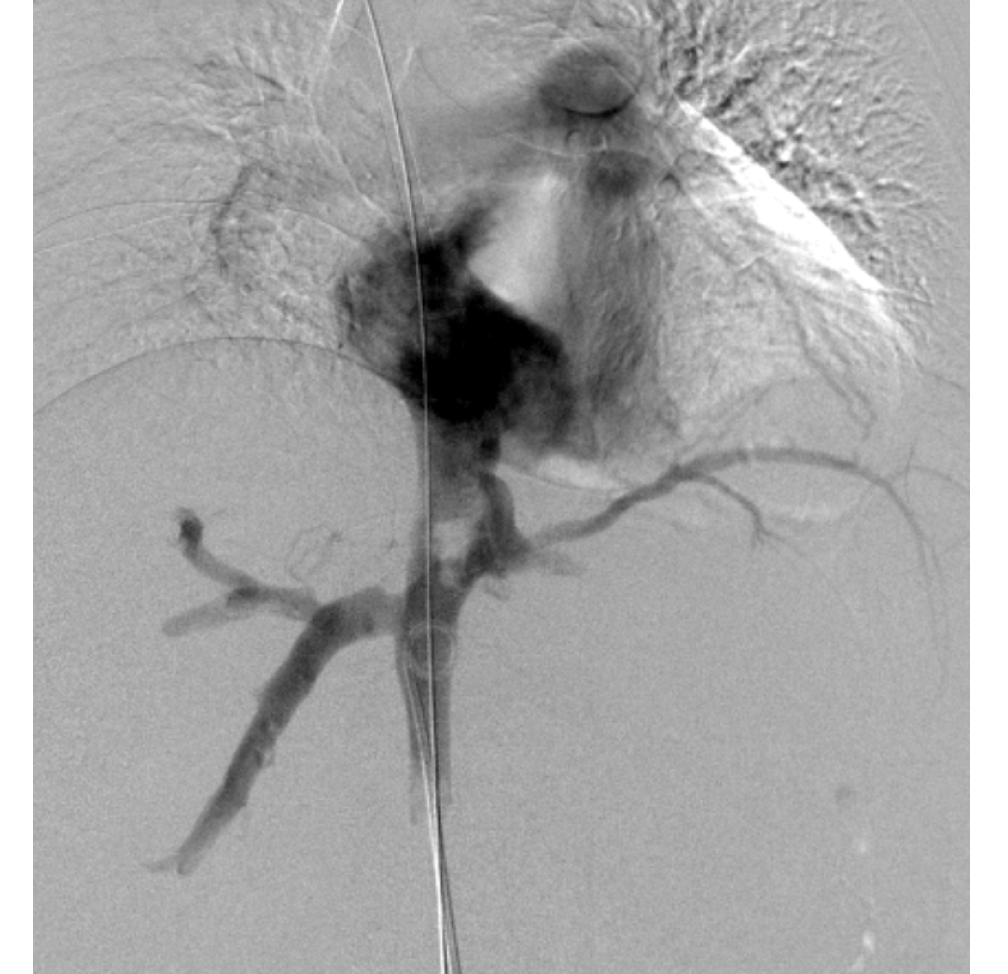

Linfangiografía con embolización del conducto torácico